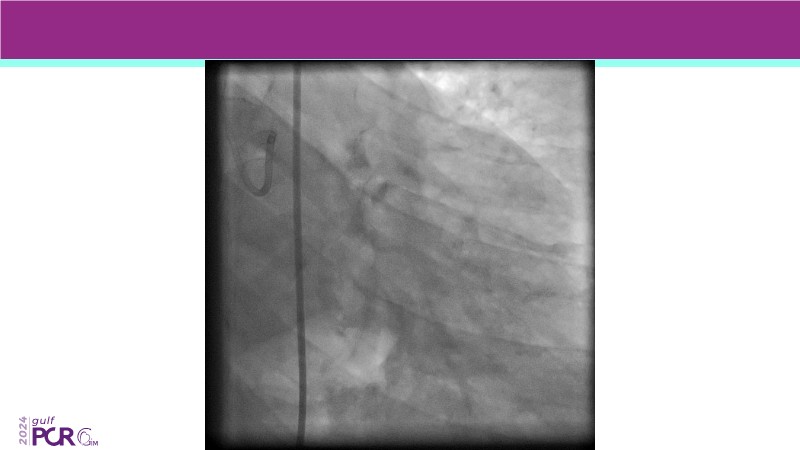

Explore the future of complex PCI with Meril Life’s advanced solutions. Learn about thin-strut platforms, dedicated stents for side branches and diffuse lesions, the role of drug-eluting balloons in metal-free PCI, and the clinical potential of the Myval THV technology.

- To discover your next gen complex PCI toolkit with thin strut platforms and dedicated stenting solutions for managing side branch and long diffused lesions

- To achieve goals of metal-free PCI in your patients using drug eluting balloons

- To learn about the novel Myval THV technology, its key features, procedural and clinical benefits and learn about the clinical data in a vast cohort of patient population